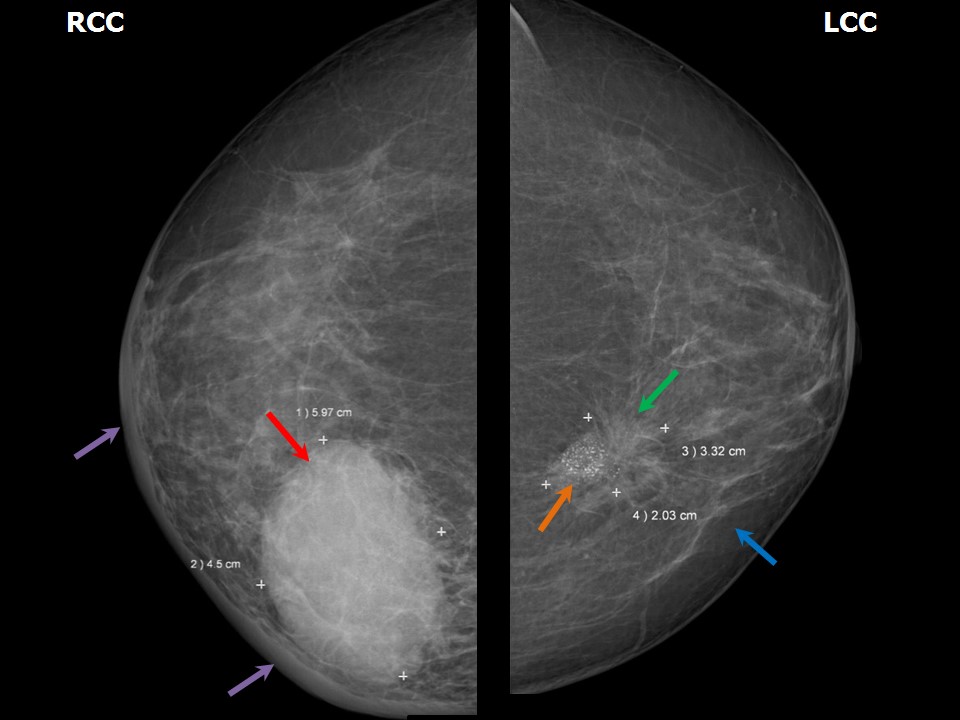

Atlas of breast cancer early detection What Is Stage 2 Ductal Breast Cancer Stage 2 breast cancer means that the cancer is either in the breast or in the nearby lymph nodes or both. Stage 2 breast cancer means your tumor is at least 1 centimeter (cm) in size and has spread to lymph nodes. The earliest stage breast cancers are stage 0 (carcinoma in situ). What are the breast cancer stages? What. What Is Stage 2 Ductal Breast Cancer.